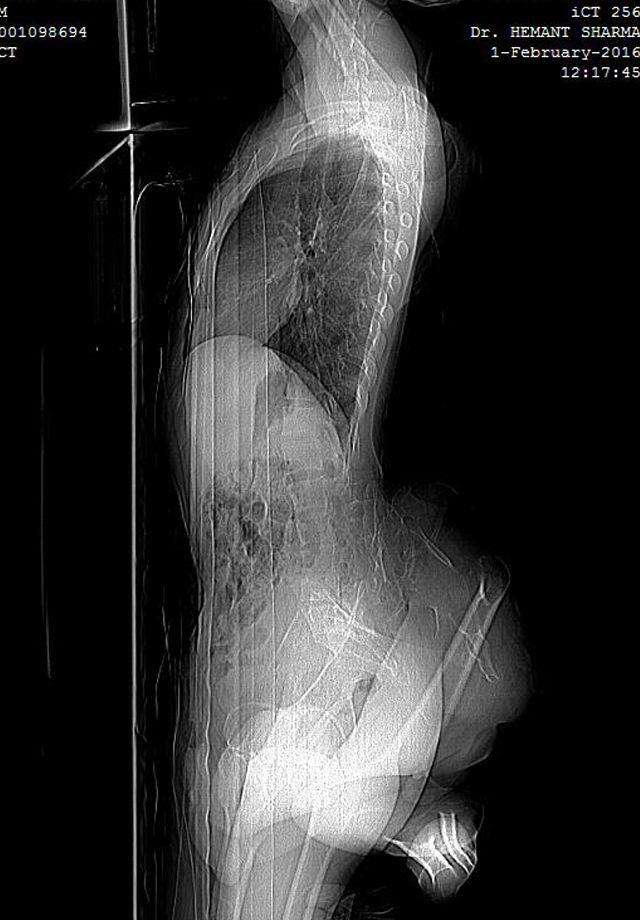

ԼԱՅՖՀնդկաստանի բնակիչ 22-ամյա Արուն Կումարն առանց բուժումների ապրում է 4 ոտքով: Ճիշտ է՝ դրանից երկուսն ընդհանրապես չեն գործում և ամենայն հավանականությամբ դրանք չզարգացած երկվորյակ եղբոր ոտքերն են: Այսօր արդեն հնդիկ երիտասարդը խնդրում է բժիշկներին ազատել իրեն մակաբույծ ոտքերից: